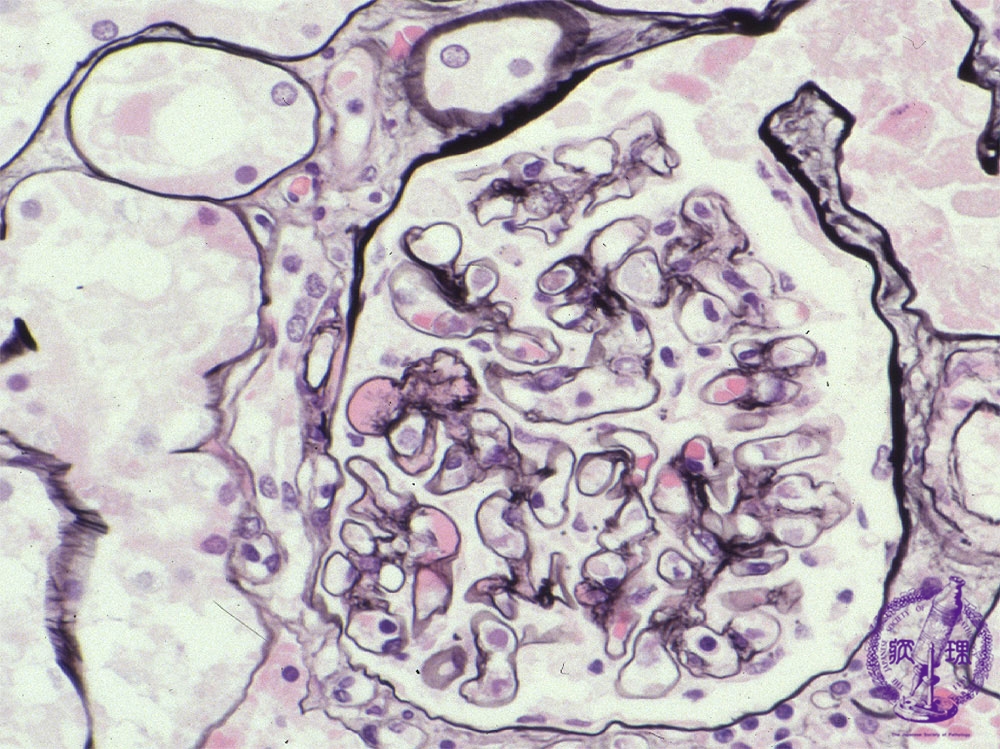

- ★(4)IgA nephropathy

Microscopic findings ( PAM, high power view): In the mesangium, there are hemispheric deposits (red arrows) corresponding to IgA deposition.